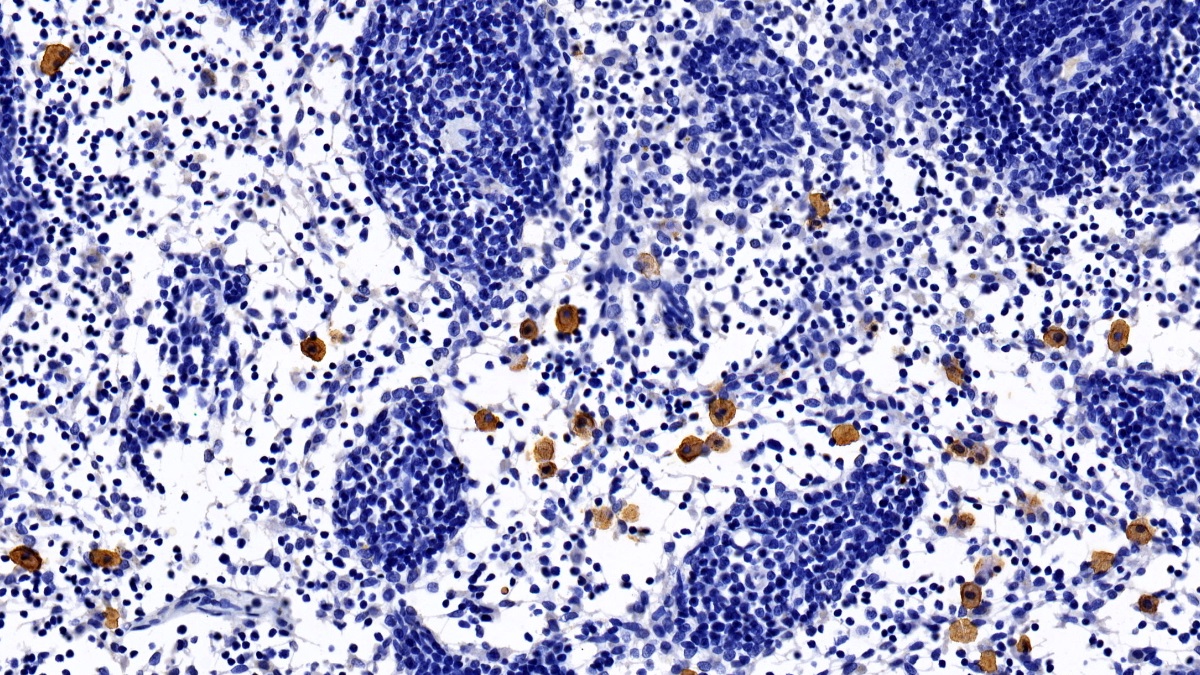

Polyclonal Antibody to Cluster Of Differentiation 23 (CD23)

Product No.: PAB582Hu01

Organism species: Homo sapiens (Human)

Monoclonal Antibody to Cluster Of Differentiation 23 (CD23)

Product No.: MAB582Hu22

Organism species: Homo sapiens (Human)